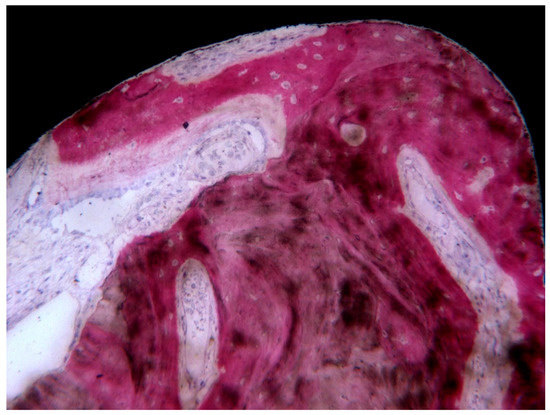

3. Results